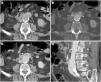

Cortes axiales del mismo paciente del vídeo 2. Tomografía computarizada basal (A) y en fases arterial (B) y portal (C) que demuestra pérdida del plano graso de separación (*) entre el injerto y la tercera porción duodenal (d) con extravasación activa de contraste intravenoso hacia la luz duodenal evidente desde la fase arterial. Reconstrucción en el plano coronal (D).

Fístula aortoduodenal primaria en varón de 90 años con hematemesis y dolor abdominal intenso en contexto de síndrome aórtico agudo. La tomografía computarizada (TC) basal muestra un gran coágulo de 40 UH en el estómago (A) y un aneurisma aórtico calcificado (a) con pérdida del plano graso de separación con la luz duodenal (d) (B). La TC con contraste intravenoso (CIV) en fase arterial (C) muestra una úlcera penetrante (flecha) y extravasación activa de CIV (punta de flecha) hacia el duodeno. Las reconstrucciones MIP en planos coronal (D) y sagital (E) muestran el flap intimomedial (flecha) y el jet de CIV (punta de flecha).

Fístula aortoentérica secundaria en varón de 77 años con antecedente de bypass aortobifemoral que actualmente presenta episodio de sangrado gastrointestinal con hematoquecia masiva, distensión abdominal y pulsos distales débiles. La tomografía computarizada basal (A), en fases arterial (B), portal (C) y la reconstrucción sagital MIP (D) muestran un desgarro intimomedial (flecha) que afecta a la superficie anterior del injerto contactando con la tercera porción del duodeno (d). Se observa asimismo extravasación del contraste aórtico al tracto gastrointestinal (punta de flecha).